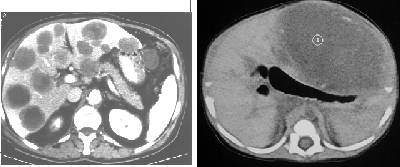

picture at left CT shows  multiple liver metastases throughout the liver and below CT with large metastasis in the right lobe of the liver

see CT of the normal liver, CT normal  liver, CT with multiple liver mets, CT advanced liver mets